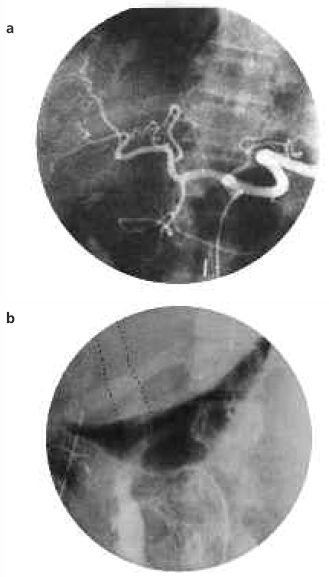

The child was prepared for cadaver liver transplantation and required blood transfusions and antibiotic therapy with good enteral feeding. He was discharged with some clinical improvement and put on the waiting list for a blood group A liver. Approximately 1 month later, the child was admitted with anemia (hemoglobin 7.0 g/dL) and a more-advanced hyperbilirubinemia (total bilirubin, 9.2 mg; direct bilirubin, 6.0 mg). It was during this time that the parents were informed about living-related partial liver donations. The mother, a 31-year-old woman with blood group A, volunteered to be the donor. Human leukocyte antigen (HLA) typing showed haploidentity, with the crossmatch being negative. The hematologic, biochemical, and urological analyses and the scintigraphic, radiologic, and tomographic evaluations of the donor showed no abnormality. Angiographic evaluation showed the recipient and donor hepatic and left hepatic arteries to be suitable (Figure la, b).

Figure 1. Normal hepatic angiograms for (a) the recipient and (b) donor.